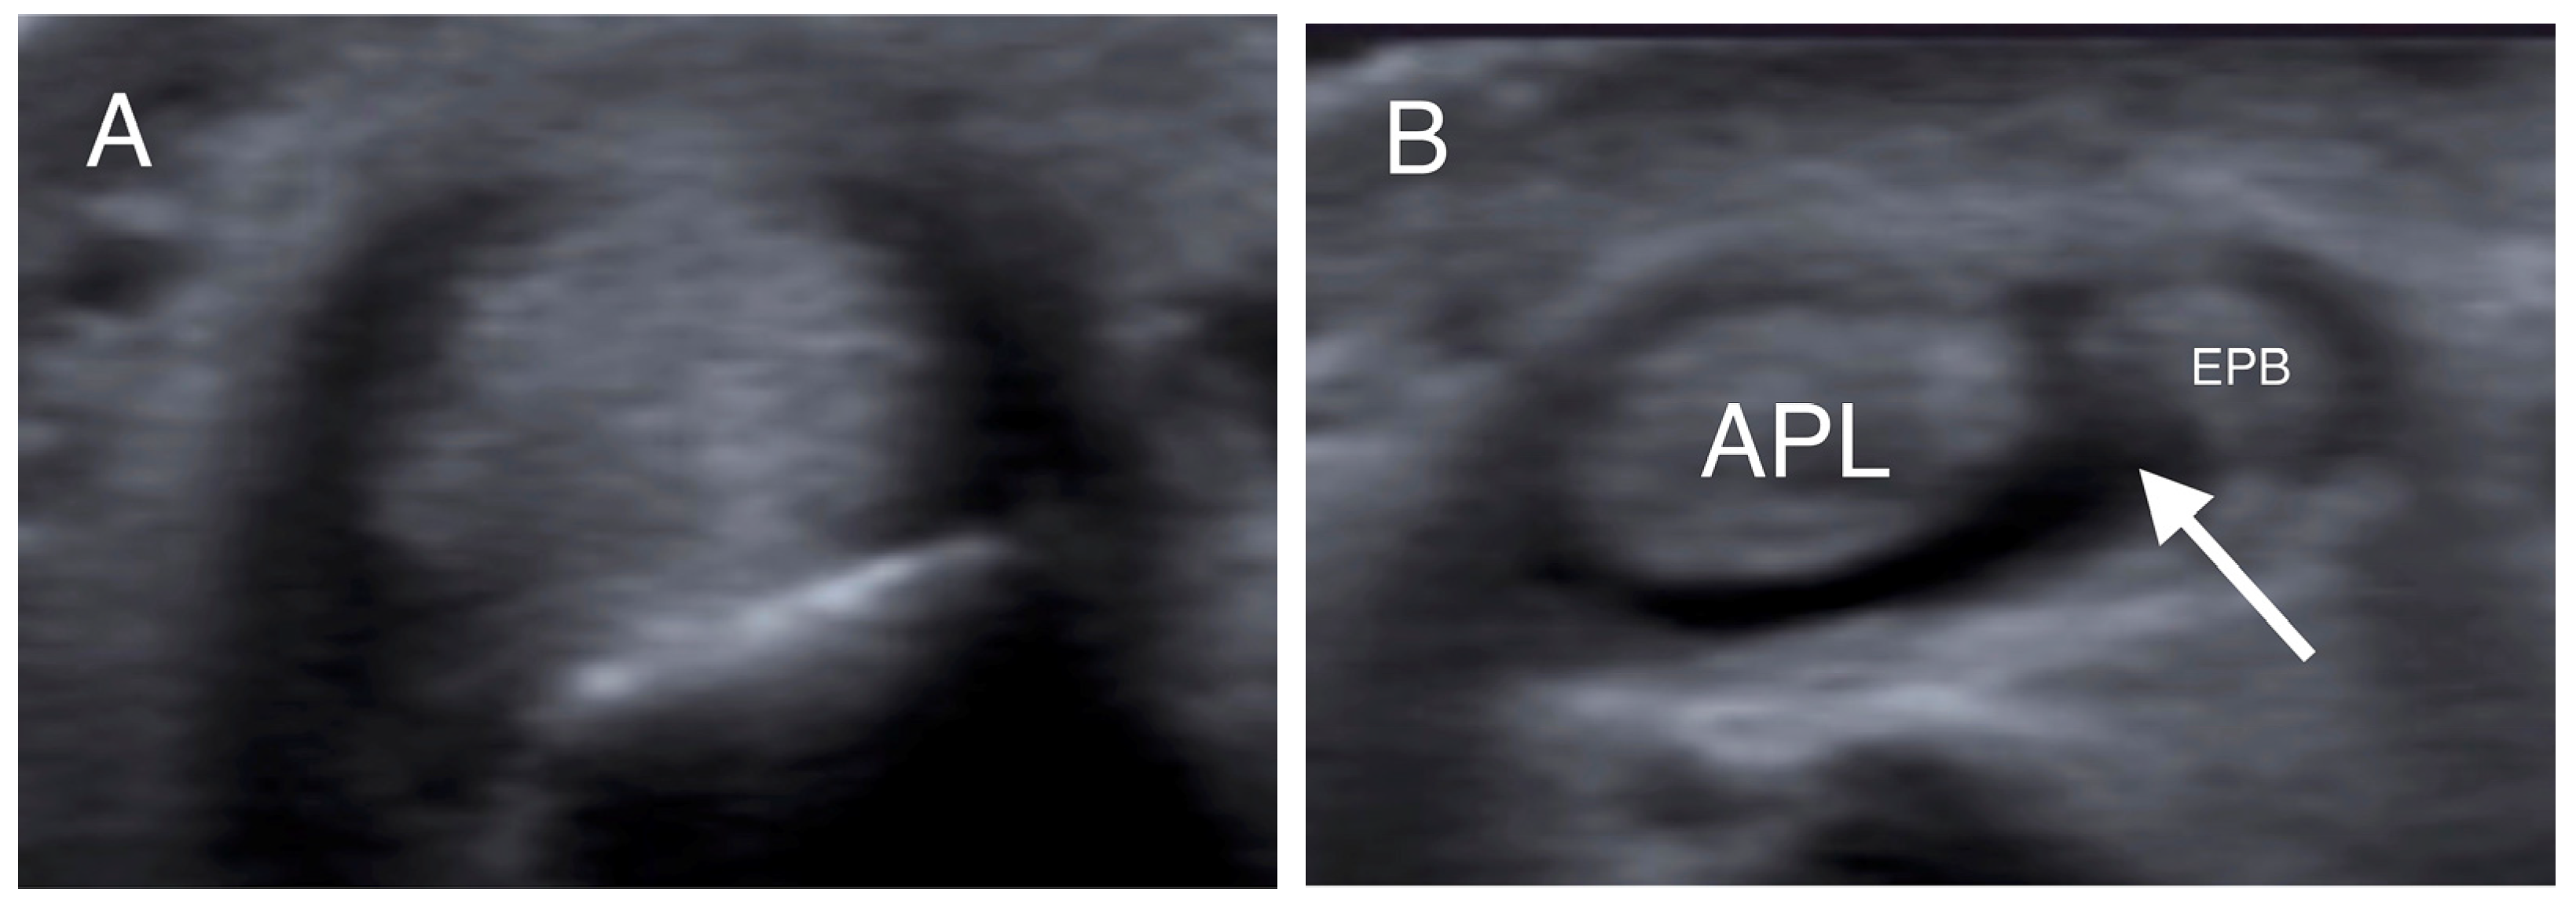

- Choi, S.J.; Ahn, J.H.; Lee, Y.J.; Ryu, D.S.; Lee, J.H.; Jung, S.M.; Park, M.S.; Lee, K.W. De Quervain Disease: US Identification of Anatomic Variations in the First Extensor Compartment with an Emphasis on Subcompartmentalization. Radiology 2011, 260, 480–486. [Google Scholar] [CrossRef]

- Kwon, B.C.; Choi, S.J.; Koh, S.H.; Shin, D.J.; Baek, G.H. Sonographic Identification of the Intracompartmental Septum in de Quervain’s Disease. Clin. Orthop. Relat. Res. 2010, 468, 2129–2134. [Google Scholar] [CrossRef]

- Abi-Rafeh, J.; Mojtahed Jaberi, M.; Kazan, R.; Alabdulkarim, A.; Boily, M.; Thibaudeau, S. Utility of Ultrasonography and Significance of Surgical Anatomy in the Management of de Quervain Disease: A Systematic Review and Meta-Analysis. Plast. Reconstr. Surg. 2022, 149, 420–434. [Google Scholar] [CrossRef] [PubMed]

| Intracompartmental septum | 27 (54%) |